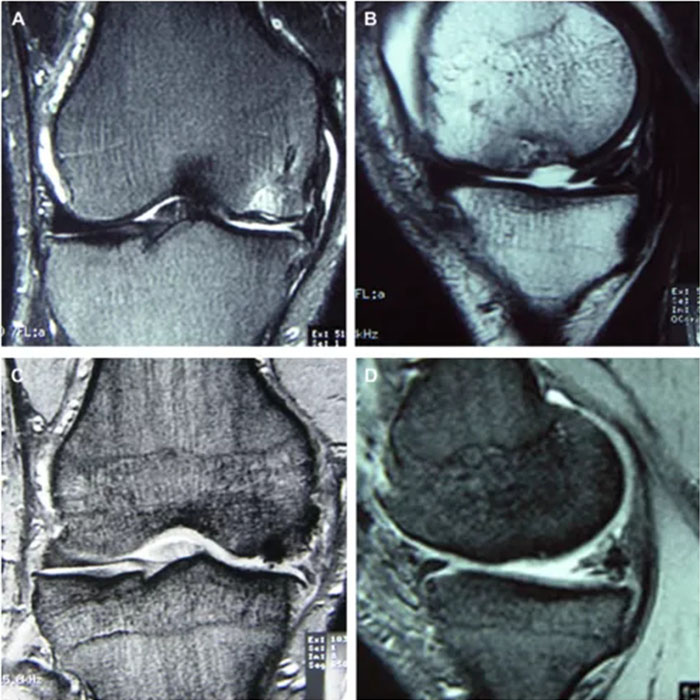

MSCs已被應用于臨床,對于軟骨的修復同樣收到了不錯的療效。一項研究中,受試者是一位31歲的男子柔道運動員,因右膝遭遇傷病而出現間斷性疼痛。股骨內側髁負重區發現20-30毫米全層軟骨缺損。在患者知情同意的情況下,用其自身的MSCs治療軟骨損傷。術前4周,從患者髂骨吸取骨髓,去除紅細胞后,擴增剩余的細胞。收集貼壁細胞并將其植入到膠原凝膠中,然后將膠原凝膠轉移至股骨內側髁軟骨缺損處,其中種植體被自身骨膜瓣覆蓋。結果顯示,在術后7個月,通過關節內窺鏡檢查發現,軟骨缺損部位被光滑組織所覆蓋(圖4)。術后1年,通過磁共振成像發現,受損部位軟骨水腫消失(圖5),臨床癥狀明顯改善,患者恢復了先前的活動水平,并且右膝不再疼痛,也沒有其他并發癥出現[3]。

A、B:術前磁共振成像。股骨內側髁有明顯的缺損,軟骨下水腫,內側半月板的后部已退化。C、D:術后1年的磁共振成像。軟骨不再水腫,但修復區軟骨和軟骨下形態不規則。